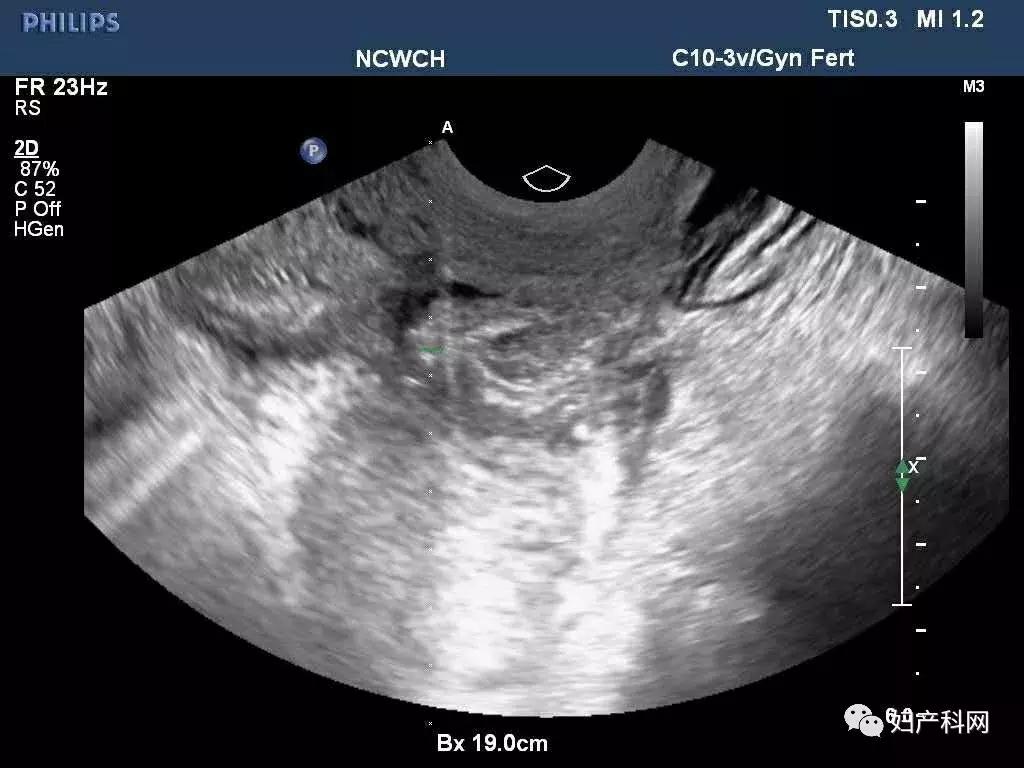

前几天这位患者再次来我们门诊复查,之前因为卵巢囊肿过大,超声甚至很难找到右侧正常卵巢组织,这一次可以轻松的发现了,囊肿也没有复发,当然后续还需要进行持续的随访。

我们给这位患者选择的是经阴道卵巢囊肿穿刺+无水酒精固化,术中见右侧卵巢囊肿分为2房,分别从2房中抽出了约100ml巧克力样粘稠液体,共计200ml,每个房分别注入了50ml的无水酒精固化15分钟后抽出,术中同时放置了一枚曼月乐。